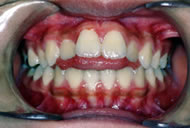

出っ歯を気にして来院された10歳の男子です。上顎前突症例として矯正治療を開始いたしました。上顎成長抑制のため上顎にヘッドギアーと咬合挙上床を装着し前期治療を行い非抜歯でエッジワイズ治療へ移行いたしました。前期治療に2年、後期治療に2年6カ月を要し治療費は前後期で84万円(税抜)となりました。上顎の前突感かの強いケースでしたが、適切な時期から開始することで、非抜歯で矯正治療を行うことが出来ました。

初診時